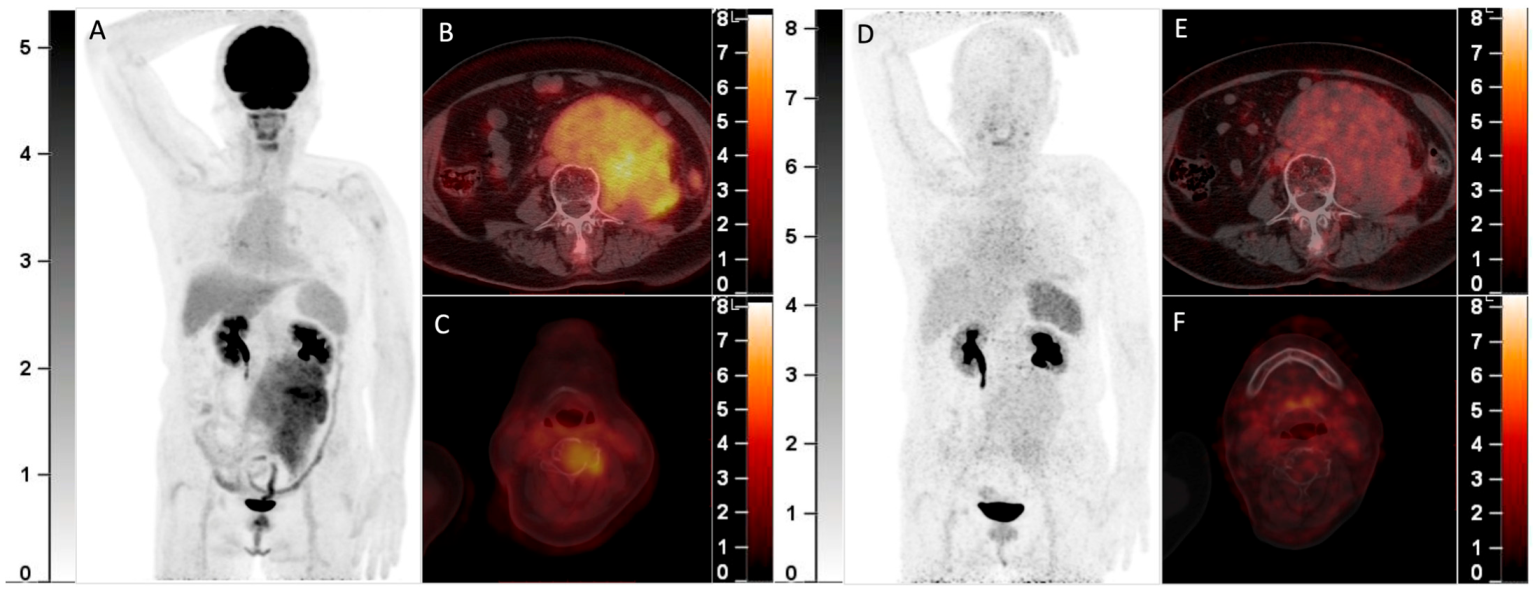

A 70-year-old woman with smoldering MM was found to have a solitary plasmacytoma in the frontal bone that was surgically resected one year ago. Recently, she complained of backache and was found with a retroperitoneal mass. Elevation of the monoclonal protein (19.0 g/L) and the presence of IgA-λ in serum immunofixation electrophoresis and infiltration of plasma cells (17.5%) in bone marrow aspiration confirmed the recurrence of MM. 18F-FDG PET/CT was then performed. The MIP image (A) showed an FDG-avid mass in the abdomen. The axial fusion images (B,C) showed the mass was located in the retroperitoneum with uneven FDG distribution (B, SUVmax 5.7). Furthermore, several bone marrow lesions with increased FDG uptake and lytic bone destruction were found in the occipital bone, C4 vertebra, and right 8th rib (C, SUVmax 4.1). She was also included in the clinical trial and underwent 68Ga-Pentixafor PET/CT (D, MIP image; E,F, axial fusion images). However, the retroperitoneal mass and the bone marrow lesions did not demonstrate increased uptake of 68Ga-Pentixafor. She then received chemotherapy against MM, and the retroperitoneal mass disappeared after 2 cycles of chemotherapy. 68Ga-Pentixafor, a CXCR4-targeted agent, has recently been introduced in MM [1,2,3,4]. Our recent study demonstrated 68Ga-Pentixafor had a significantly higher sensitivity than 18F-FDG in detecting newly diagnosed MM2. However, 68Ga-Pentixafor was inferior to 18F-FDG in the current two cases of recurrent MM with extensive EMD. CXCR4 is overexpressed in myeloma cells and is responsible for plasma cells’ homing to the bone marrow niche [5,6]. Development of EMD in MM is associated with CXCR4/CXCL12 downregulation through cell adhesion disruption [7,8,9]. In line with the current cases, Lapa C. et al.’s study found that some EMDs were exclusively identified by 18F-FDG and were not sensitive to 68Ga-Pentixafor [1]. Thus, the significantly lower uptake than 18F-FDG of recurrent MM with EMD may be a potential limitation of 68Ga-Pentixafor in assessing MM.